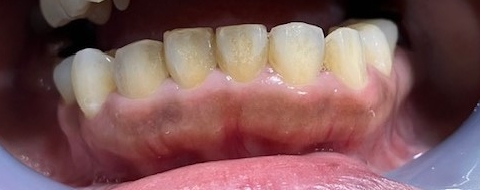

この患者様の場合は、上の歯のセラミック治療をする前でしたので、下の歯8本でお試しホワイトイニングを行いました。

歯が自然な白さになることにより、口元の清潔感が出るだけでなく、上の歯のセラミックの色を選択する幅も広くなりました。